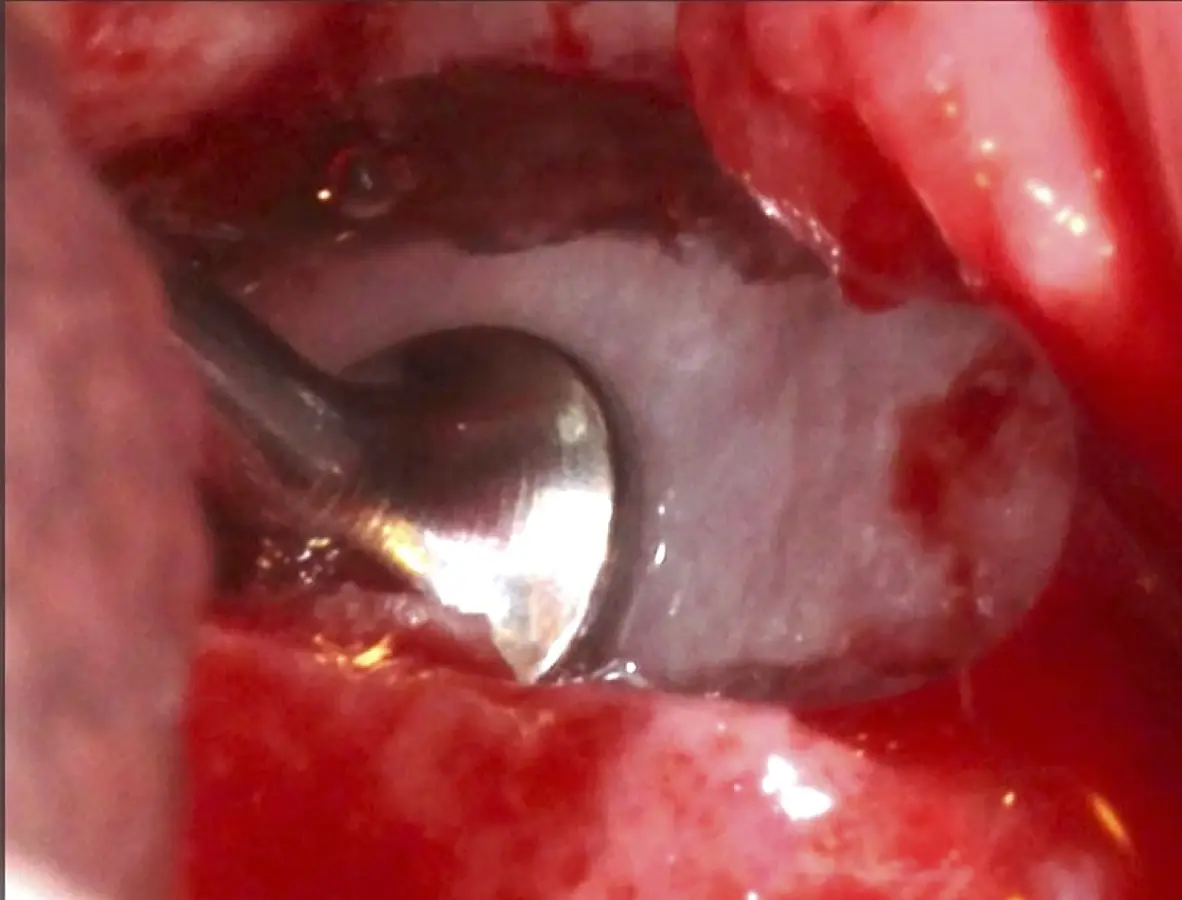

Se inicia la elevación de la membrana de Schneider con el inserto redondeado no cortante en forma de disco, empleando movimientos suaves. El levantamiento puede complementarse con elevadores convencionales, siguiendo la dirección mesiodistal. La fase de desprendimiento inicia con el piso y sigue hacia la pared mesial para terminar, y de ser necesario, hacia la pared posterior. Existen diversos insertos con angulaciones y longitudes para mayor accesibilidad16 (Figura 1).

Figura 1. Incisión y levantamiento de colgajo a espesor total.

Inserto de presión hidráulica iniciando el desprendimiento de la membrana de Schneider (a, b ).

Figura 7. Inserto de presión hidráulica iniciando el desprendimiento de la membrana de Schneider (a, b ).